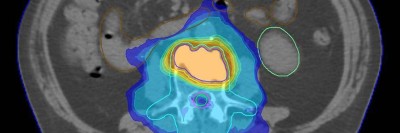

TKI und simultane thorakale Radiotherapie: ein vielversprechender Ansatz?

• NSCLC

• Kommentierte Studie

Die Ergebnisse einer aktuellen Studie liefern interessante Erkenntnisse zur Rolle einer kombinierten Tyrosinkinaseinhibitor(TKI)- und thorakalen Radiotherapie (TRT) bei oligoorganmetastasiertem, EGFR-mutiertem nichtkleinzelligem Lungenkarzinom (NSCLC). Jedoch sind einige Aspekte für die Bewertung der Arbeit zu berücksichtigen.

Operation/© andrys lukowski / stock.adobe.com (Symbolbild mit Fotomodell), Arzt impft Patient/© FG Trade / Getty Images / iStock (Symbolbild mit Fotomodell), Koloskopie/© Kzenon / stock.adobe.com (Symbolbild mit Fotomodellen), Bestrahlungsplans einer Wirbelsäulenmetastase eines oligometastasierten Prostatakarzinoms/© Springer Medizin Verlag GmbH, Blutprobe wird bei Patient abgenommen/© Tashi-Delek / Getty Images / iStock(Symbolbild mit Fotomodellen), Endobronchialer Befund mit exophytischem Tumor im Bereich des rechten Oberlappens/© Möller, M., Schütte, W. / all rights reserved Springer Medizin Verlag GmbH, Eine ältere Frau bekommt eine intravenöse Therapie/© peopleimages.com / stock.adobe.com, Mann gibt Anweisungen auf Baustelle/© Oliver Raupach - Fotolia (Symbolbild mit Fotomodell), CT-Thorax mit Verdacht auf Lungenkrebs/© Springer Medizin Verlag GmbH, Nicht-kleinzelliges Bronchialkarzinom/© windcatcher / Getty Images / iStock, Immuncheckpointinhibitoren binden an Krebszelloberflächenproteine /© Juan Gärtner / stock.adobe.com, Einem Mann wird Fieber gemessen/© eggeeggjiew / Getty Images / iStock (Symbolbild mit Fotomodell), Mann stützt den Kopf in die Hände/© Charday Penn / Getty Images / iStock (Symbolbild mit Fotomodell), Bronchoskopie/© Schroll S et al. / all rights reserved Springer Medizin Verlag GmbH, NSCLC in der PET-CT/© A. Schäffler, Bestrahlung eines Lungenkarzinoms/© Springer Medizin Verlag GmbH, Bildgebung einer rechts pulmonalen Raumforderung der Lunge/© Klotz, L.V., Welcker, K. / all rights reserved Springer Medizin Verlag GmbH, Search Icon, Endoskopische Befunde des Magenkarzinoms/© Probst, A., Messmann, H. / all rights reserved Springer Medizin Verlag GmbH, Hand hält Laborröhrchen/© Kunstzeug / stock.adobe.com (Symbolbild mit Fotomodell), Radiologin richtet Mammographiescreening ein/© LIGHTFIELD STUDIOS / stock.adobe.com (Symbolbild mit Fotomodellen), Diffus großzelliges B-Zell-Lymphom (DLBCL)/© David A Litman / stock.adobe.com